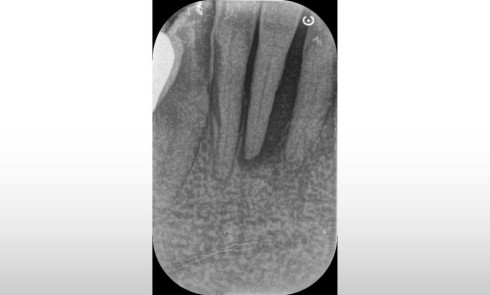

Si elle n’est pas structurellement plus fragile qu’une dent pulpée, la dent dépulpée présente tout de même un risque accru de fracture dû à la flexion de ses cuspides sous contrainte, favorisée par la perte de substance coronaire, surtout lorsque la continuité du cerclage dentinaire péri-cervical est rompue. La cavité d’accès endodontique, profonde, donne lieu à des parois hautes et fines, et la perte des crêtes marginales favorise davantage la flexion de ces parois lors des fonctions occlusales. Les restaurations adhésives peuvent permettre de compenser la perte de substance coronaire tout en rétablissant la cohésion des structures dentaires par l’intermédiaire de la restauration. On rétablit ainsi une unité bio-fonctionnelle dent/restauration dans la mesure où la résistance intrinsèque du type de restauration choisi permet d’atteindre et de pérenniser ces objectifs. Cette démarche est l’une des principales motivations d’indication des restaurations partielles collées indirectes, en particulier en vitrocéramique renforcée, qui permettent, dans bien des situations, de rétablir les aspects esthétiques et fonctionnels de la dent, tout en préservant ses tissus originels bien mieux qu’une restauration corono-­périphérique dont la préparation nécessite souvent un sacrifice tissulaire complémentaire important. Dans des situations de moindre délabrement, les matériaux de restauration directs peuvent aussi atteindre ces mêmes objectifs avec une approche bien plus conservatrice et un coût tissulaire de mise en œuvre encore réduit, pour peu qu’ils présentent les capacités d’adhésion et de résistance suffisantes.

Comme ce fut le cas pour les vitrocéramiques, l’évolution des matériaux a cherché à augmenter la résistance intrinsèque des résines composites en y augmentant la proportion et/ou la nature de ses charges. Les fibres de verre ont ainsi été employées à dessein.